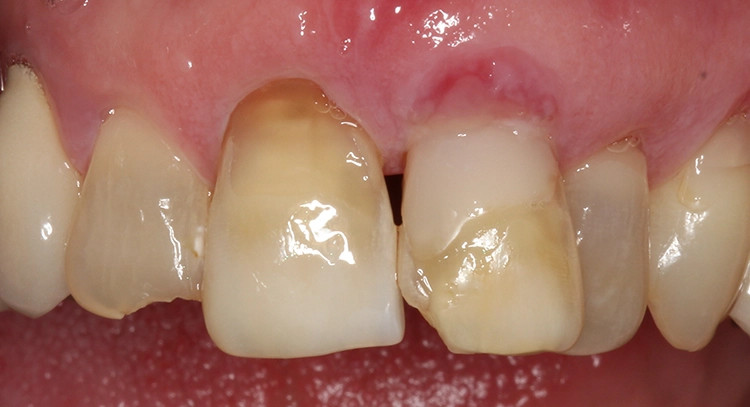

Bei der 61-jährigen Patientin imponierten unterschiedlichste Befunde, die ein ästhetisches Gesamterscheinungsbild gerade der Oberkieferschneidezähne deutlich beeinträchtigten (Ausgangsbefund Bild oben): Labiale und inzisale Zahnhartsubstanzdefekte unterschiedlichster Ausprägung an allen Inzisivi, Verfärbungen der Zähne, eine Fehlstellung sowie multiple Rezessionen und keilförmige Zahnhalsdefekte, die zum Teil von diversen Vorbehandlern mit Zahnhalsfüllungen versorgt worden waren. Es zeigte sich ein Gewebeüberschuss in regio 22, der zumindest teilweise durch die Elongation und Retrusion des Zahnes 22 bedingt zu sein schien. Diese Kombination führte zu einem disharmonischen Gingivaverlauf im Ober- und im Unterkiefer.

Die Patientin wurde eingehend über die Möglichkeiten und das operative Vorgehen der präprothetischen Mukogingivalchirurgie aufgeklärt: Die „Zahnfleischästhetik“ kann durch einen Rückgang, auch aber durch einen Überschuss von Gewebe negativ beeinflusst werden. Korrekturen von diesen Missverhältnissen können demnach durch unterschiedliche chirurgische Maßnahmen vorgenommen werden. Aufgrund von Statur und Gesichtsform der Patientin erschienen die Zähne 13 bis 11 nicht zu lang, weshalb gemeinsam mit der Patientin lediglich eine Korrektur des Gingivaverlaufes im 2. Quadranten eingeplant wurde.

So sollte an den Zähnen 21 und 23 eine Rezessionsdeckung mit Verdickung des Gewebes und an Zahn 22 eine chirurgische Kronenverlängerung durch Exzision der Gingiva ohne Osteotomie erfolgen (Low-Crest-Typ). Der Verlauf der Schneidekantenlängen und die Zahnstellung sollten in einem 2. Schritt durch Vollkeramikteilkronen bzw. Veneers mit Inzisalfassung harmonisiert werden. In der Behandlungsplanung dieses Falles kam erschwerend hinzu, dass 3 verschiedene parodontalchirurgische Behandlungsindikationen zusammenkamen: